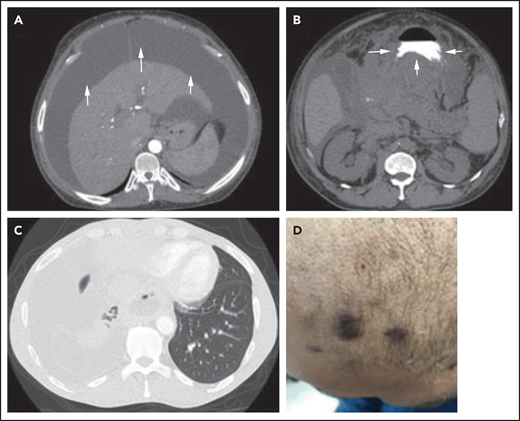

Because KSHV results in a systemic infection, it is important to evaluate any patient who is KSHV+ for KSHV-associated diseases, particularly if the patient is HIV+. KSHV-associated diseases frequently co-occur (Figure 2C-D). Therefore, it is critical for any KSHV+ patient with rapidly enlarging lymphadenopathy, an effusion, or clinical deterioration to have an extensive multidisciplinary clinical and laboratory evaluation, including positron emission tomography/computed tomography scans, tissue biopsies, effusion flow cytometry, and evaluation for opportunistic infections and other AIDS-related lymphomas.

Three different presentations of PEL. (A) Isolated malignant ascites in a patient with classic PEL (arrows). (B) EC/solid PEL infiltrating the stomach (arrows). Notice the mass displacing the oral contrast. (C-D) Isolated malignant right-sided pleural effusion (C) with concurrent KS (D). Notice the collapse of the right lung compared with the left (C), with characteristic purple KS lesions located on the side of the face in the same patient (D).

PEL is a rare, aggressive B-cell non-Hodgkin lymphoma defined by the presence of KSHV.3 PEL classically occurs in pleural, peritoneal, and pericardial spaces but can occur in other cavities, including blood vessels and the subarachnoid space.60-63 The solid EC variant of PEL usually arises in lymph nodes or in extranodal sites, particularly the gastrointestinal tract and skin (Figure 2B).

The symptoms experienced by patients with PEL result from (1) the malignant effusion or EC mass, which, depending on its location, can lead to shortness of breath, abdominal distention, and chest pain (Figure 2A-C)62,65,67,68,71,75, and (2) KSHV and its associated conditions. Because KSHV is the tumor driver in PEL/EC-PEL, it is not uncommon for patients to present with other KSHV-associated malignancies/conditions (eg, KS or KSHV-MCD; Figure 1D; Table 1).62,65,67-69,71,75 One-third to 75% of patients with PEL present with concurrent or prior KS, and 33% have or have a history of KSHV-MCD (Figure 1D; Table 1). KSHV can also cause immune dysregulation, inducing elevations of huIL-10, huIL-6, and vIL-6, which can result in many of the constitutional and laboratory abnormalities, including fever, cachexia, edema, and anemia.72 Severe immune dysregulation can occur, leading to KICS, which in combination with other KSHV-associated conditions negatively affects prognosis.70,72